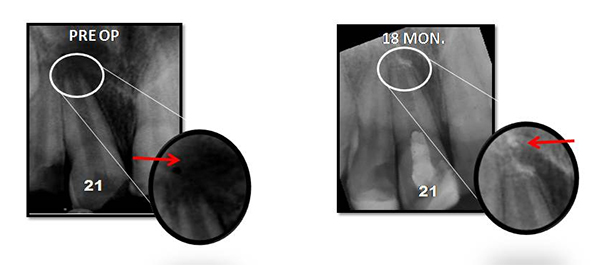

Regenerative Endodontic Procedure -

Regenerative Endodontic Procedure

Naseem Shah -

PRF Mediated REP in 21 with 18 Months Follow Up

Complete Bony Healing, Apex Closed, Lateral Wall Thickening- 15.5%

Dental Treatment

Tanisha Konai -

PRP Mediated REP in 21 with 18 months follow up

Bone healing, Apical PDL formed, Apex Closed, Calcific Bridge formed in 21.

Vitality Positive

Amanulla -

PRF Mediated REP in 22 with 18 months Follow up

Complete Bony Healing, Calcific Bridge Formed.

PRF Mediated REP in 21 with 26 Months Follow Up

Complete Bony Healing, Apex Closed, Lateral Dentinal Wall Thickened, PDL Apically